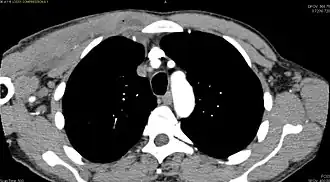

Diagnostic methodDiagnostic method used for PM includes ultrasound, CT scan and MRI. Ultrasound can be helpful in showing muscular heterogeneity or a purulent collection but it is not useful during the first stage of the disease. CT scan can confirm the diagnosis before abscesses occur with enlargement of the involved muscles and hypodensity when abscess is present, terogenous attenuation and fluid collection with rim enhancement can be found. MRI is useful to assess PM and determine its localization and extension